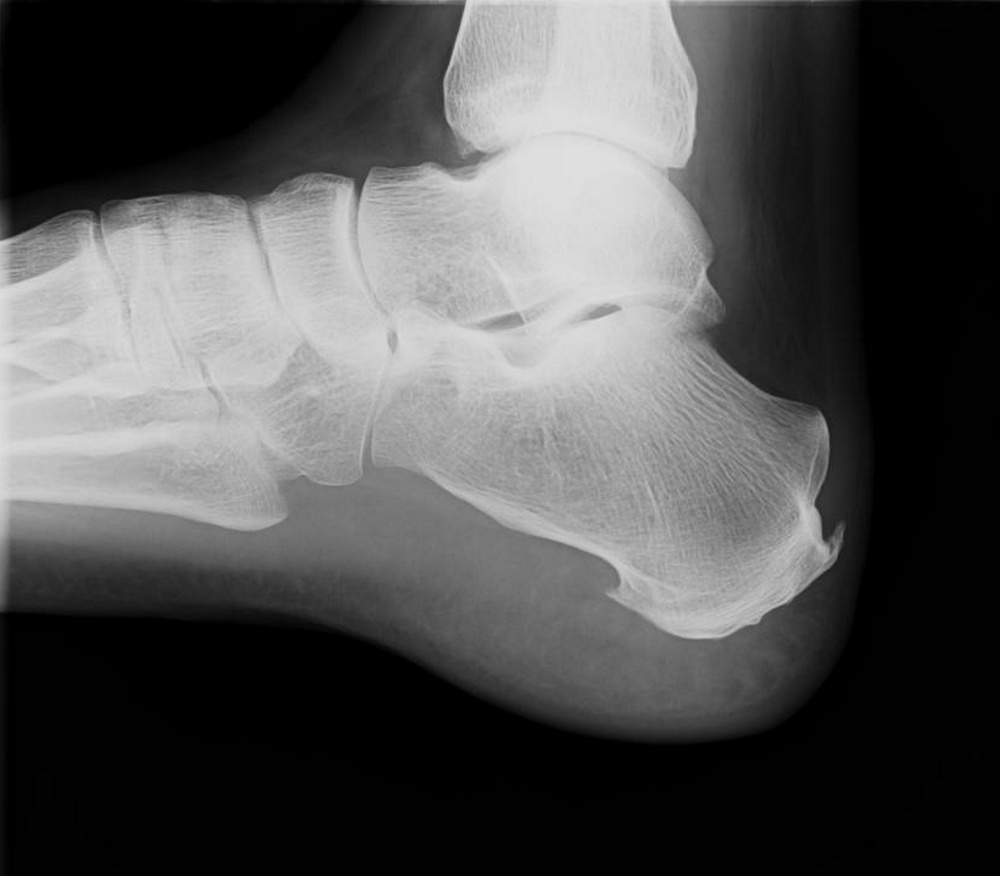

Pro ilustraci: na rentgenovém snímku si všimněte ostrých výstupků na patě. U tohoto klienta je patrná patní ostruha nejen na spodní části paty (plantární), ale dokonce i na zadním úponu Achillovy šlachy (dorzální). Tento klient se desítky let intenzivně věnuje profesi tesaře.

V okamžiku, kdy začnete pociťovat bolestivé příznaky, je patní ostruha většinou již patrná při RTG (rentgenovém) vyšetření, které zobrazí kostní výrůstek v ose dlouhodobě přetěžované šlachy. Není však úplně nezbytné nechat se ozařovat rentgenovými paprsky. Patní ostruhu, ale dokonce i zánět ještě bez průkazu patní ostruhy, lze dobře zobrazit na diagnostickém ultrazvuku, který patří mezi neinvazivní (organismus nezatěžující) metody.